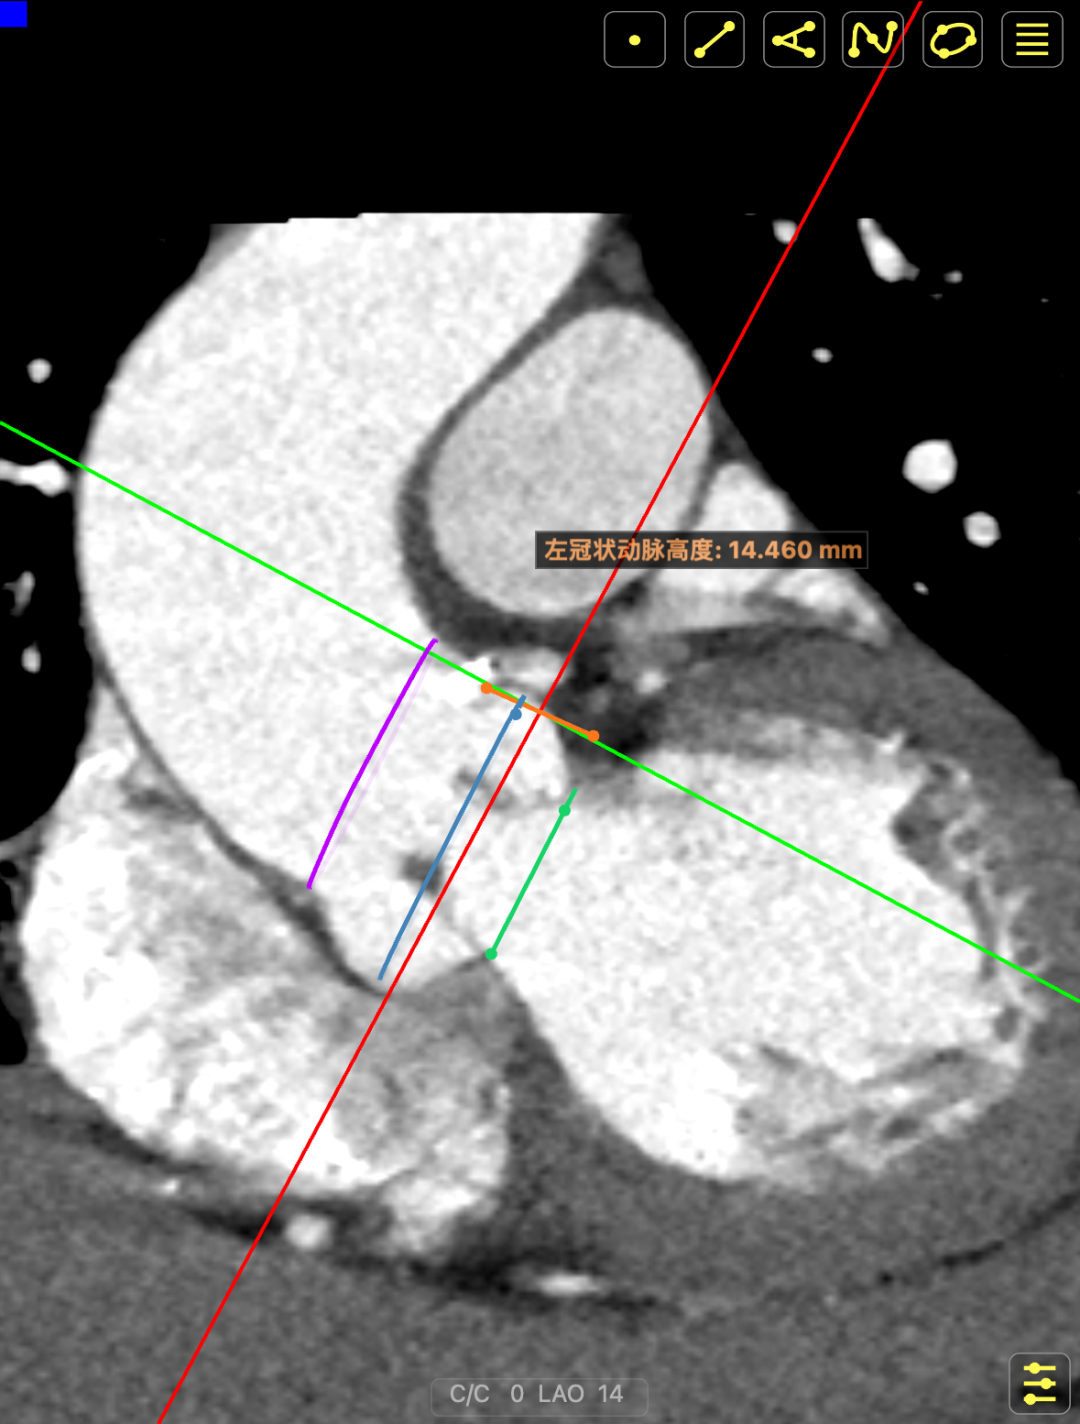

术前CT提示

主动脉瓣多发钙化,主动脉瓣为type0型二叶瓣中重度钙化。主动脉瓣环面积折算直径约24mm。患者双侧冠脉开口高度可(左冠14.46mm,右冠18.29mm),主动脉升弓降部管壁不规则并钙化斑块影,主动脉弓并龛影。升主动脉管径36mm,降主动脉管径22mm。腹主动脉、双侧髂动脉管壁不规则并可见钙化斑块影,双侧髂总动脉及其分支髂内动脉管腔轻度狭窄。

CT影像